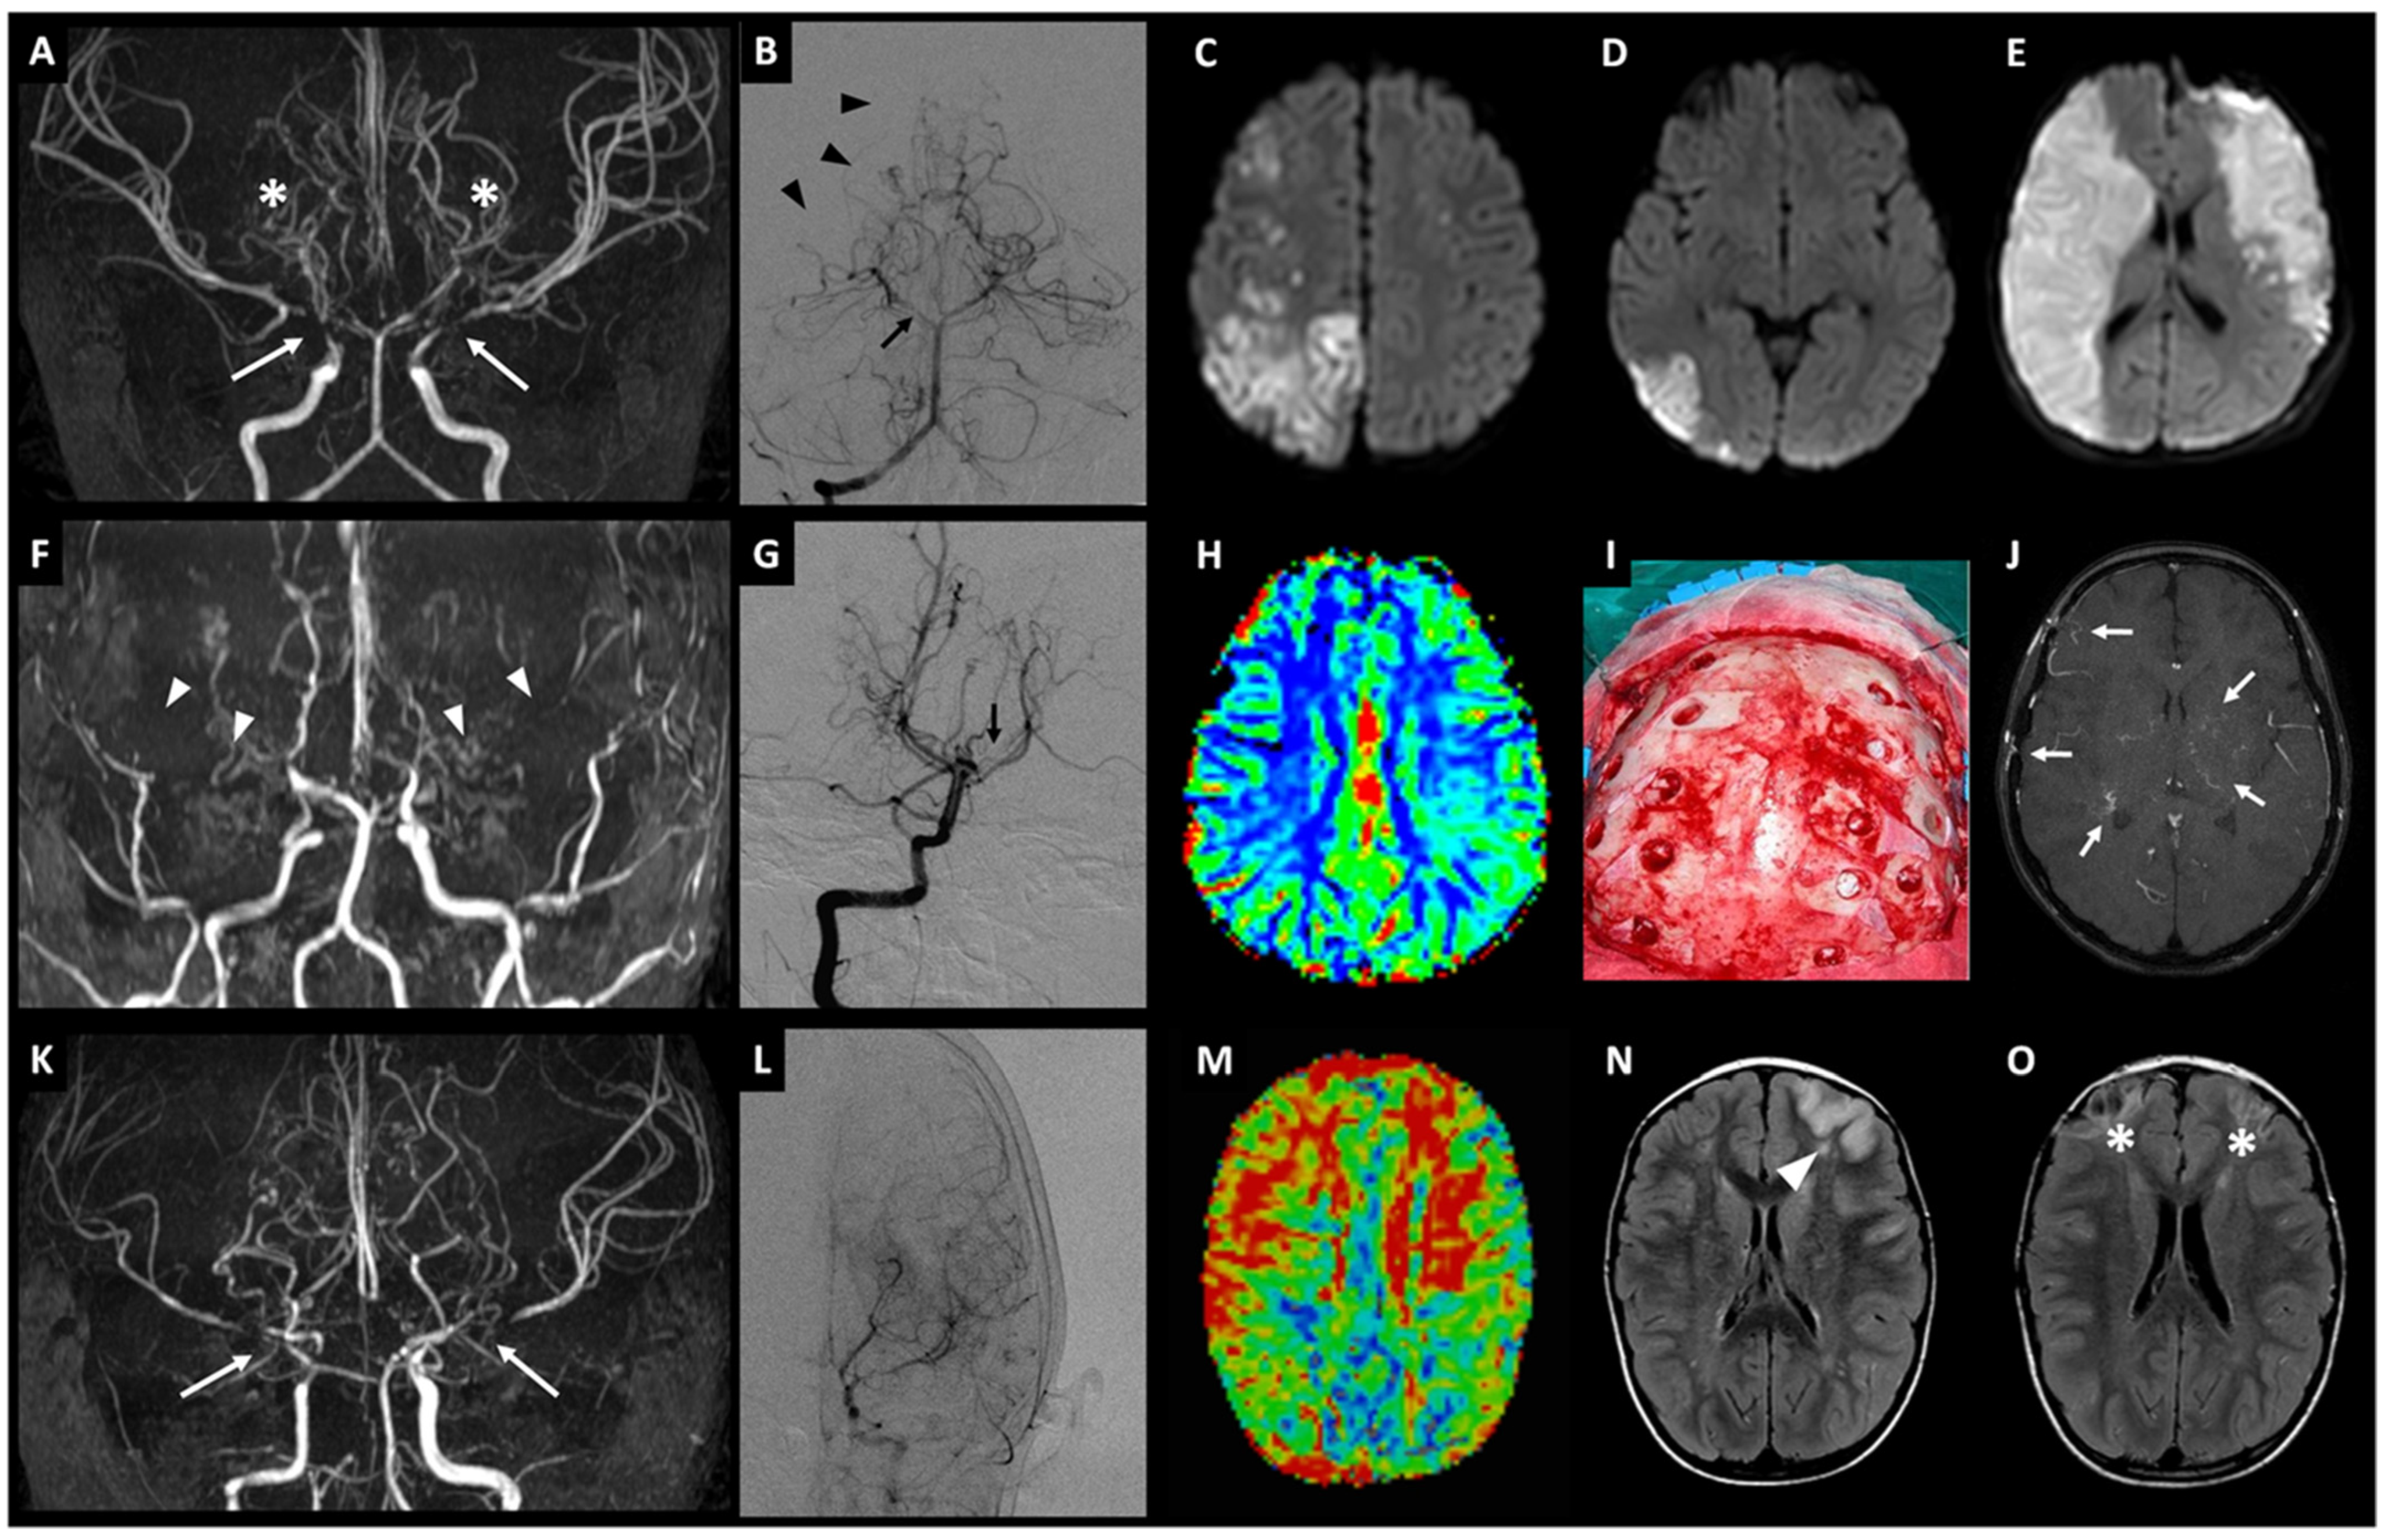

2.1. Family A

2.2. Family B

2.3. Family C